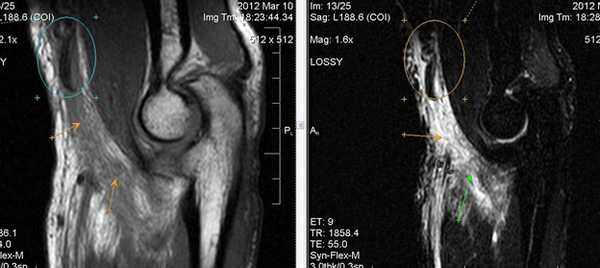

Травматические изменения локтевого сустава

МР-признаки незначительного синовита локтевого сустава; отечность мягких тканей (трехглавой мышцы плеча и глубокого сгибателя пальцев) нижней поверхности сустава; нельзя исключить минимальные проявления посттравматического липоартрита.

МР-картина структурных изменений в виде фокуса и очага отека трабекулярной костной ткани локтевого отростка локтевой кости и головки лучевой кости. Нерезко выраженный синовит.

МР-картина частичного разрыва сухожилия двуглавой мышцы плеча. Признаки частичного повреждения дистальных отделов сухожилия плечевой мышцы, в большей степени в месте прикрепления. Начальные проявления артроза локтевого сустава. Синовит. Отек медиальных отделов периартикулярных мягких тканей.

МР-томография позволяет определять изменения на ранних стадиях, когда рентгенологический метод является неинформативным. Возможность визуализации мягкотканных структур делает МРТ-исследование локтевого сустава методом выбора в диагностике различных патологических состояний.